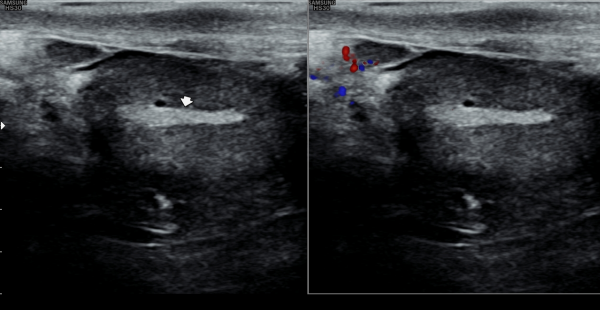

수년전 부터 하복부 통증과 사정시 혈정액을 주소로 여러 비뇨기과와 상급병원에서 치료를 했으나 증상의 호전이 없다고 내원당일 검사한 경직장 전립선 초음파 검사상 사정관 입구에 결석과 사정관의 낭종이 관찰되는 초음파 사진입니다.

The transrectal prostate ultrasound image taken on the day of the patient's first visit shows a stone at the ejaculatory duct opening and a cyst in the ejaculatory duct.

The patient had been experiencing lower abdominal pain and hematospermia during ejaculation for several years, and had received treatment at multiple urology clinics and advanced hospitals without symptom improvement.

내원당일 경직장 전립선 초음파 검사상 정낭의 낭종이 커져 있고 정낭내 결석이 관찰되는 측면 경직장 초음파 사진입니다.